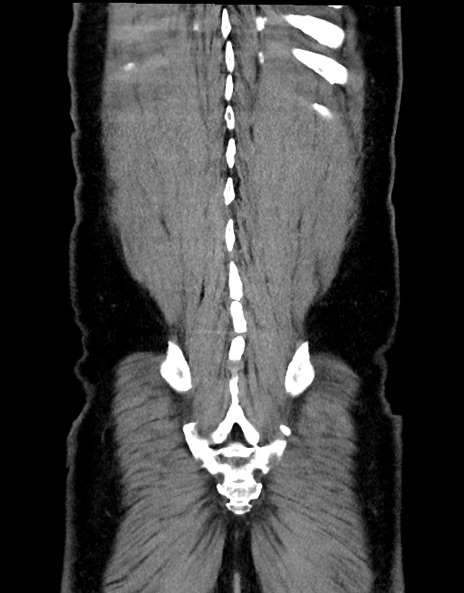

症例15(冠状断像)

【症例】70歳代男性

【主訴】腹痛

【現病歴】今朝から腹痛あり。全体的に痛い。特に左上の方。排ガスが今日はない。冷や汗が出る。

【既往歴】直腸癌術後

【身体所見】左側腹部〜上腹部に圧痛あり。腹膜刺激症状明らかなではない。軽度反跳痛。左下腹部に術後瘢痕あり。

【データ】WBC 7700、CRP 0.02